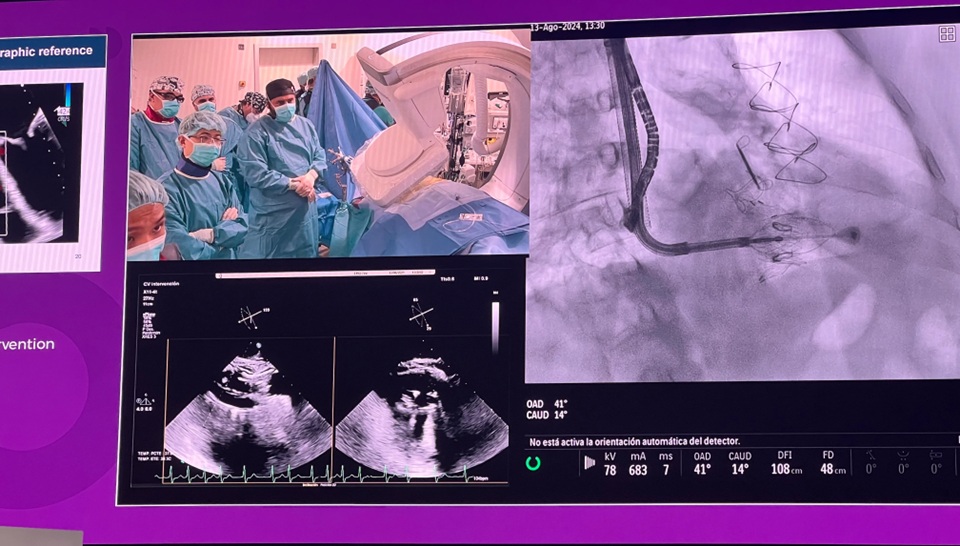

隨后由來自西班牙維哥-阿爾瓦羅昆奎羅醫(yī)院(Hospital Álvaro Cunqueiro, Vigo, Spain)的 Rodrigo Estevez-Loureiro 教授在大會主會場的經(jīng)導(dǎo)管介入瓣膜新技術(shù)環(huán)節(jié),帶來了一例 LuX-Valve Plus 手術(shù)錄播,對手術(shù)植入的步驟和關(guān)鍵要點進行了詳細深入的介紹。同時,臺上的多位討論嘉賓也結(jié)合他們的 LuX-Valve Plus 手術(shù)經(jīng)驗進行了深入的探討。來自香港瑪麗皇后醫(yī)院(Queen Mary Hospital, Hong Kong, China)的 Simon Lam 教授分享了 LuX-Valve Plus 在術(shù)前有起搏導(dǎo)線病人中的植入經(jīng)驗,來自巴西圣保羅(Rede D'Or São Luiz, São Paulo, Brazil)的 Vinicius Esteves 教授補充了 LuX-Valve Plus 獨特的非徑向支撐力設(shè)計,能夠?qū)崿F(xiàn)非常低的術(shù)后起搏器植入率,來自法國波爾多大學(xué)醫(yī)院(CHU de Bordeaux, Bordeaux, France)的 Lionel Leroux 教授則分享了其在LuX-Valve Plus歐洲臨床試驗過程中,對于大尺寸瓣環(huán)植入的優(yōu)異結(jié)果。